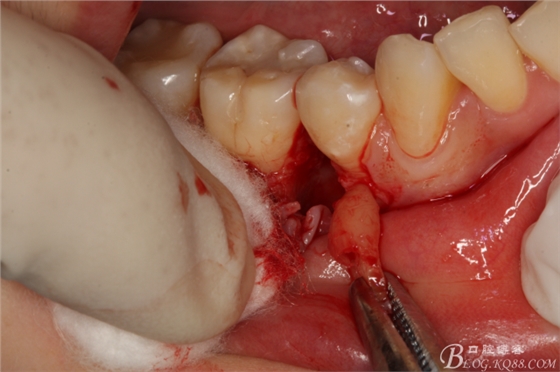

圖7.翻小瓣。暴露45牙根斷面

圖8.高速球鉆去骨約3mm.

圖9.暴露45頰側(cè)根面約1/2.牙根與44、46牙根緊緊相鄰。無法直接用挺。